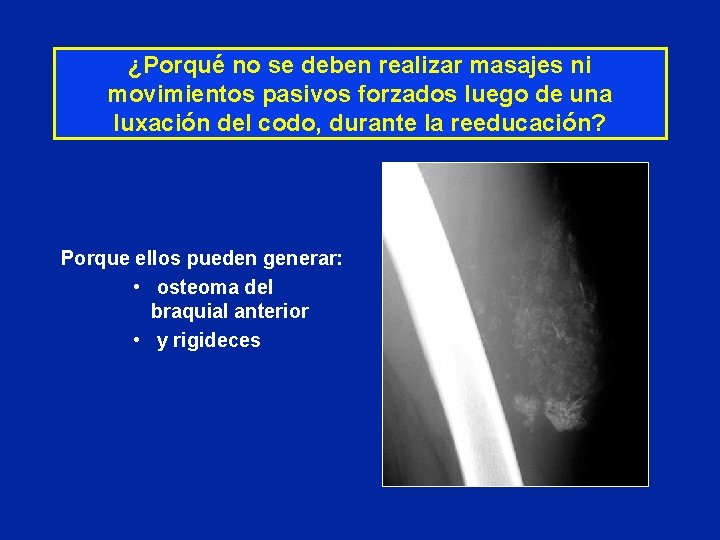

¿Porqué no se deben realizar masajes ni movimientos pasivos forzados luego de una luxación del codo, durante la reeducación? Porque ellos pueden generar: • osteoma del braquial anterior • y rigideces

¿Porqué no se debe realizar masajes o movimientos pasivos forzados durante la reeducación de una luxación de codo ?

¿Porqué no se debe realizar masajes o movimientos pasivos forzados durante la reeducación de una luxación de codo ? Porque pueden generar • osteoma del braquial anterior • y rigidez